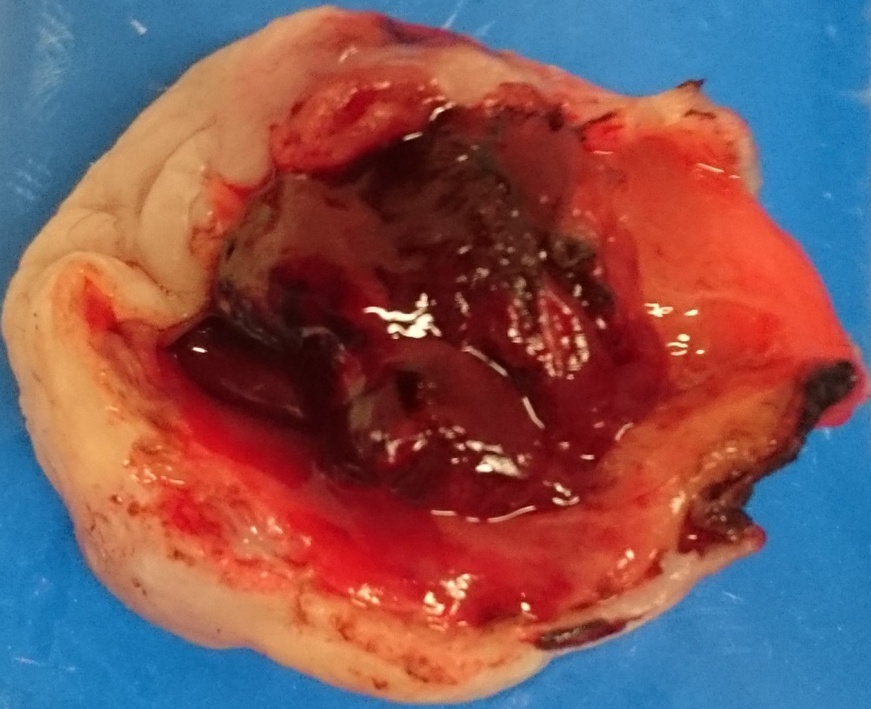

Χειρουργικά παρασκευάσματα εξαιρεθέντων ενδομητριωμάτων (Ευγενική παραχώρηση Dr. V. Penopoulos)